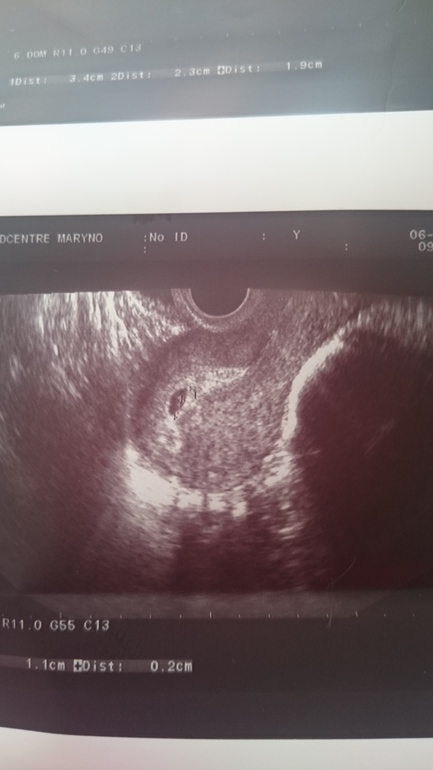

Я пришла только что с повторного УЗИ!!! Девочки, нас нашли, Б есть, маточная, срок 4 недельки! Я не верю, мне надо чтоб меня ущипнули, это как сон, год прошел после ВБ и вот оно чудо, сколько было слез и истерик, как я боялась что ничего уже не получится! Девочки какое же это счастье, во мне зародилась новая жизн, дай Бог чтоб все дальше было хорошо!!!!

Вот моя бусинка )))